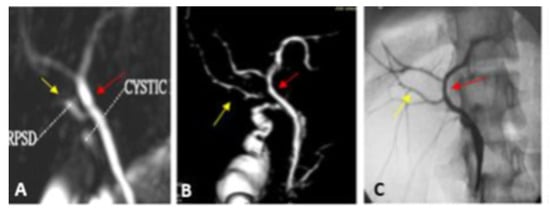

| Type I | The RPSD drains into the proximal part of the RHD (distance more than 1 cm from the hepatic confluence) | 23 (65.7) | 22 (62.9) | Very short RHD |

| Type II | Trifurcation | 4 (11.4) | 6 (17.1) | |

| Type IV | Insertion of RHD in the cystic duct | 3 (8.6) | 3 (8.6) | |

| Type VII Unclassified | Trifurcation + accessory duct | 1 (2.9) | - | The acute angle between RPSD and RASD |